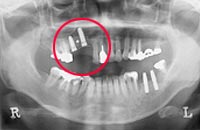

臼歯部にインプラントを打とうとした際に上顎洞までの距離が短く、そのままではインプラントが打てない場合に行われる手術です。

ある程度自分の骨が残っている場合には、当院内の手術が可能な場合もあります。

高度なテクニックを必要とするため、当院では提携病院にて手術を行っております。 臼歯部にインプラントを打とうとした際に上顎洞までの距離が短く、 そのままではインプラントが打てない方で、あまり自分の骨が残っていない場合、行います。